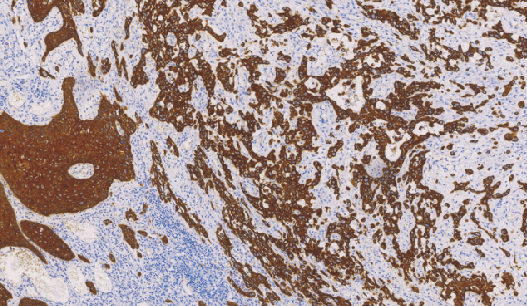

Cytokeratin5/6(CK5/6)鼠抗人细胞角蛋白5/6单克隆抗体

在正常组织中,CK5/6主要表达于鳞状上皮、导管上皮基底细胞肌上皮细胞和间皮细胞,腺上皮表达阴性。该抗体主要用于鳞癌与腺癌、间皮癌与腺癌的鉴别诊断,也可用于导管上皮良恶性增生的鉴别。

- 阳性部位:胞质

- 适用组织:石蜡切片

- 预处理:热修复